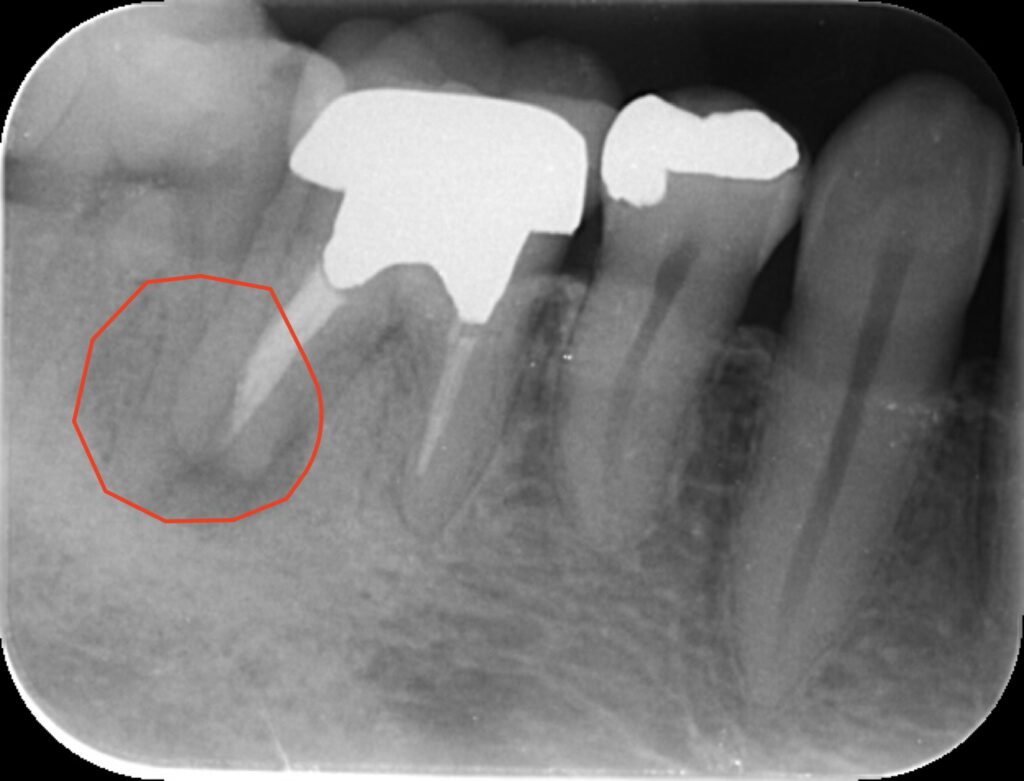

初診時の状況:

前医で「骨が溶けているので抜歯しかない」と診断されたケースです。根の先には大きな黒い影(透過像)が確認できます。確かに根尖病変は比較的大きいですが歯質が残っている今回の症例は「長持ち(Longevity)させられる」と当院では判断しました。